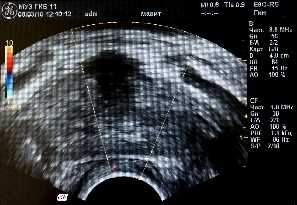

Для оценки биотканевого влияния устройства «МАВИТ» на кровообращение ПЖ и окружающие ткани у 10 больных из второй группы (ХП) до и после физиотерапевтического сеанса проводилось трансректальное ультразвуковое исследование ПЖ в режиме цветного доплеровского картирования. Изучалась линейная пиковая скорость кровотока, индекс периферического сосудистого сопротивления, а также плотность органного сосудистого рисунка.

Для оценки состояния кровотока в предстательной железе после сеанса локальной физиотерапии на устройстве «МАВИТ» у 10 больных второй группы (ХП) проведено трансректальное ультразвуковое исследование ПЖ в режиме цветного доплеровского картирования до и после лечебного сеанса, показавшее улучшение микроциркуляции в ткани предстательной железы. Применение аппарата «МАВИТ» приводит к выраженной реакции в виде усиления кровообращения по всему сосудистому коллектору (см. рис. 1 и 2). Средний показатель линейных пиковых скоростей в изученной подгруппе увеличился в 1,1 раза, уменьшилась величина индекса резистентности в 1,2 раза в сравнении с исходными данными. Средний показатель плотности сосудистого рисунка увеличился более чем в 2,5 раза.

Рис.1 Рис.2

Рисунок 1: Б-ой П., 38 лет. Доплерограмма перед сеансом физиотерапии на устройстве «МАВИТ».

Рисунок 2: Доплерограмма того же больного после сеанса физиотерапии на устройстве «МАВИТ».